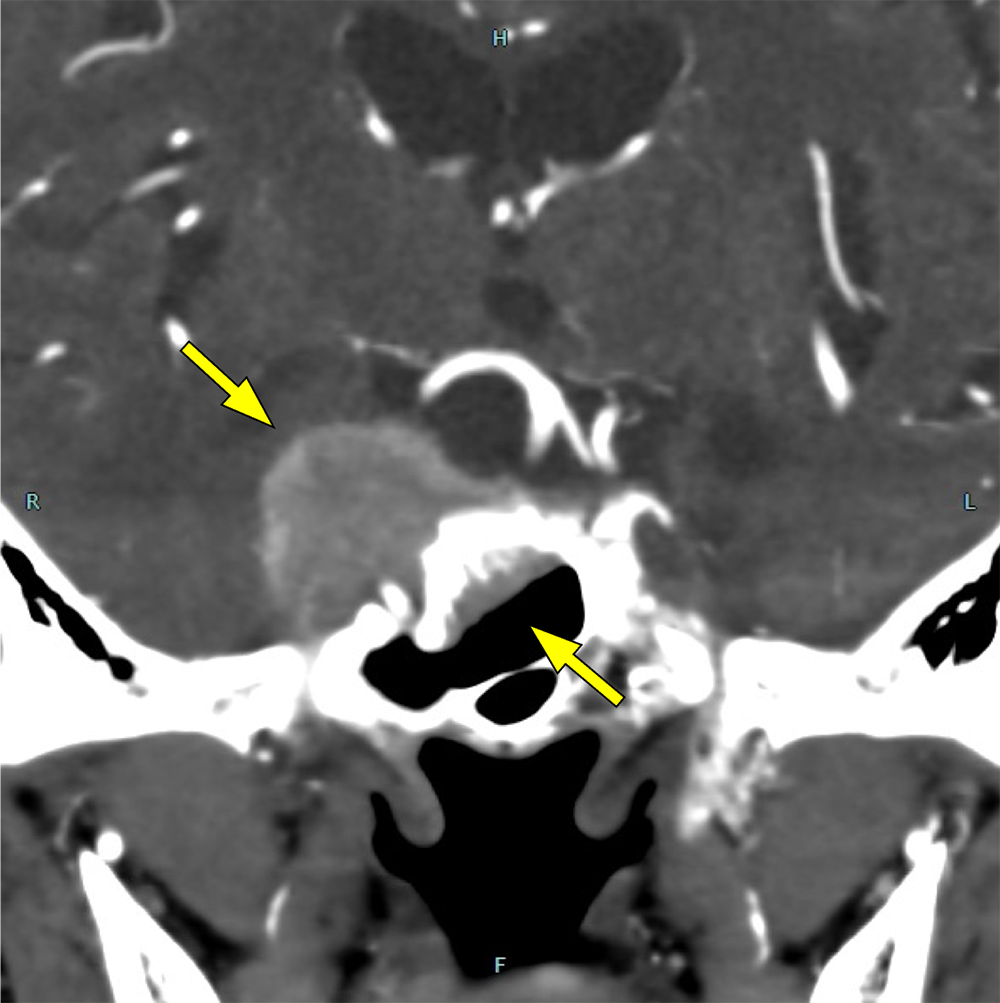

図2.造影CT(早期相)

右海綿静脈洞~蝶形骨洞の腫瘤が早期から明瞭に造影されている。

図5.造影CT(後期相)

小脳テントに沿った進展を認め、血管と同程度の強い造影効果を示している。